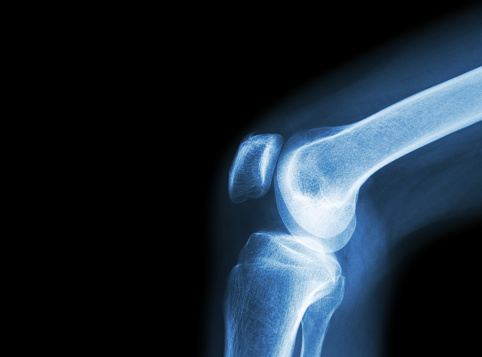

Managing arthritis during the holidays: Holiday and travel tips for arthritis sufferers

Managing arthritis during the holidays is important because arthritis pain and complications can really put a damper on your festive plans. When you’re bogged down by pain and stiffness you can’t enjoy the holidays to the fullest. To save you from suffering, here are some helpful tips to get you through the holidays – despite ...click here to read more